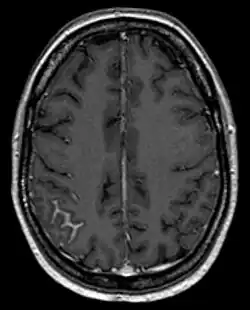

Bildgebung: Nachweis einer fokalen Meningeosis carcinomatosa bei Mammakarzinom in der Magnetresonanztomographie. Man erkennt die fokale Anreicherung (hell) in den Sulci als Zeichen einer arachnoidalen Ausbreitung rechts (links im Bild). -